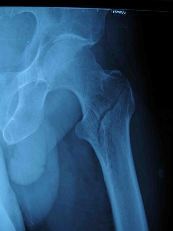

股骨粗隆间骨折

明显外伤史,患肢疼痛,活动受限。Х线片可确定骨折部位及移位情况。

病人多为老年人,伤后髋部疼痛,不能站立或行走。下肢短缩及外旋畸形明显,无移位的嵌插骨折或移位较少的稳定骨折,上述症状比较轻微。检查时可见患侧粗隆升高,局部可见肿胀及瘀斑,局部压痛明显。扣击足跟部常引起患处剧烈疼痛。往往需经X线检查后,才能确定诊断,并根据X线片进行分型。